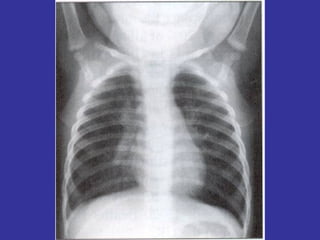

PNEUMONIA  Inflammation and infection of the lung parenchyma due to bacterial or viral  pathogens. Classified by anatomy:  Lobar, Interstitial, Bronchopneumonia Etiology: Viral:   Adenovirus, Influenza, RSV Bacterial:   Neonates:  GBS, Chlamydia, E. coli, Listeria monocytogenes  1month-6 years:  S. pneumonia, H. influenza Adolescents:  S. pneumonia, Mycoplasma pneumonia Immunocompromised:  Pseudomonas, klebsiela, Fungi, PCP

Epidemiology:   Children 2-4 years, are more susceptible than older children May follow epidemics of viral infection Winter/spring most common Day care/ kindergarten S/S:   Tachypnea,  dyspnea,  cough,  intercostal retractions, nasal flaring,  grunting,  fever,  accessory resp. muscles usage,  chest pain,  lethargy,  hypoxia, rales/crackles,  decreased  breath  sound/dullness to percussion (consolidation). LAB:   CBC:   WBC with left shift,  Blood culture (if severe picture),  Pleural fluid studies (effusion),  ABG  CXR:   Lobar consolidation ( S. pneumonia and H. influenza ),  Hilar adenopathy ( TB ),  Pneumatoceles ( S. aureus/G- ),  Bilateral diffuse infiltrate ( Mycoplasma ),  Abscess ( klebsiella ) Mycoplasma:  Presence of Cold agglutinin titers Prevention:   Pneumovax vaccine in immunocompromised children, SC Ds.

LAB:   Blood test: Eosinophilia,  Elevated serum IgE Nasal test for presence of eosinophilia Skin testing (+) best test for allergen sensitivity Provocational tests: Methacholine challenge- confirm Dx of asthma. Measure airway hyperreactivity. RAST test Immunocap PFTest  Measure degree of airway obstruction and  response of broncho dilator  Decreased PEFR  Increased TLC-FRC-RV ABG:   Decreased PO2,  initially Respiratory alkalosis (hyperventilation),  later  Respiratory acidosis (CO2 retention) CXR:   Hyperinflation, flat diaphragms, inc. peribronchial thickening, atelectasis  R/O lung malformation, or other pathology. At home:   Peak Flow Meter.  Measures PEFR (peak exp. flow rate)